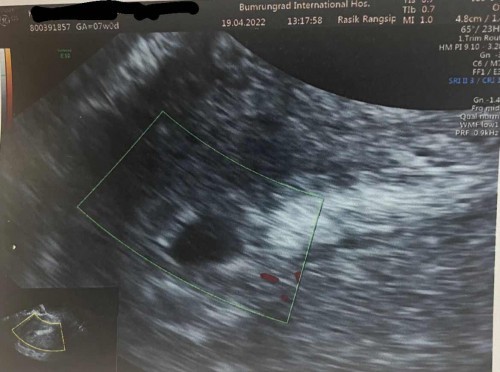

อยากมาแชร์ประสบการณ์จากที่ทำใจว่าท้องลม 100% มาวันนี้ซาวน์เจอหัวใจแล้วค่ะ :)

เรื่องมีอยู่ว่าถ้านับจากประจำเดือน วันที่เราไปซาวน์ครั้งแรกต้องเป็น 7 สัปดาห์ พอเราซาวน์ทางช่องคลอดไปพบแต่ถุงเพียง 5 มิลเองค่ะ พอเห็นคือทำใจไว้แล้ว เพราะมันควรจะเห็นตัวน้อง ถุงไข่แดง เสียงหัวใจ คุณหมอก็ยังให้ความหวังว่าอีก 1 อาทิตย์มาดูกัน อาจจะเป็นการตกไข่ช้า แต่ตัวเราก็ไม่ได้หวังเลยค่ะ เพราะเป็นคนประจำเดือนมาตรง ใจนี่โอเคทำใจวางแผนกับตัวเองว่าจะขูดมดลูกแล้ว พอมานัดซาวน์ครั้งที่ 2 แว๊บแรกที่เห็นคือรู้เลยว่าถุงตั้งครรภ์ใหญ่ขึ้น สักพักคุณหมอก็ชี้ให้ดูว่าเห็นอะไรไหม เห็นเป็นกระพริบๆ เลยค่ะ คุณหมอบอกหัวใจน้อง แล้วก็เห็นถุงไข่แดง ตัวเรานี่ทั้งงงทั้งตกใจ คือหมดหวังไปแล้ว คุณหมอเลยมาคำนวณให้ใหม่บอกเคสเราน่าจะตกไข่รวน รอบแรกที่มาซาวน์น่าจะ 4 วีคเอง จากที่คิดว่า 7 วีค มาซาวน์วันนี้น้อง 5 วีคกว่าแล้วค่ะ อยากมาแชร์ให้แม่ๆ ที่ซาวน์ไม่เจออย่าเพิ่งถอดใจแบบเรานะคะ เพราะอะไรก็เกิดขึ้นได้จริงๆ :) #ท้องแรกคะ #ท้องแรก #5week

คุณแม่ท่านใดเคยซาวน์ทางช่องคลอดแล้วพบแต่ถุงบ้างคะ 7 weeks ค่ะ

วันนี้เพิ่งไปซาวน์มาเจอแต่ถุง ไม่เจออย่างอื่นเลยค่ะ กังวลว่าจะท้องลม ตรวจเลือดค่า hcg ได้ 3,489 แม่ๆท่านใดเคยเป็นแบบนี้บ้างคะ เราไม่รู้ตัวเลยว่าท้องประจำเดือนมาล่าสุด 1 มีนา ระหว่างนั้น วันที่ 21 มีนา ฉีดโมเดอร์น่าไป เข็ม 4 วันที่ 29 มีนา ไปเล่นเจ็ทสกี วันที่ 8 เมษาพบเชื้อโควิด กินฟ้าทะลายโจรในการรักษา วันที่ 16 เมษา ตรวจปัสสาวะพบว่าตั้งครรภ์ มีอาการเหมือนประจำเดือนจะมาปวดหน่วงๆท้องน้อยเล็กน้อย #ขอบคุณล่วงหน้านะคะ #คุณแม่ๆช่วยแนะนำหน่อยค่ะ #ขอบคุณสำหรับคำตอบค่ะ #ท้องแรก #ท้องลม